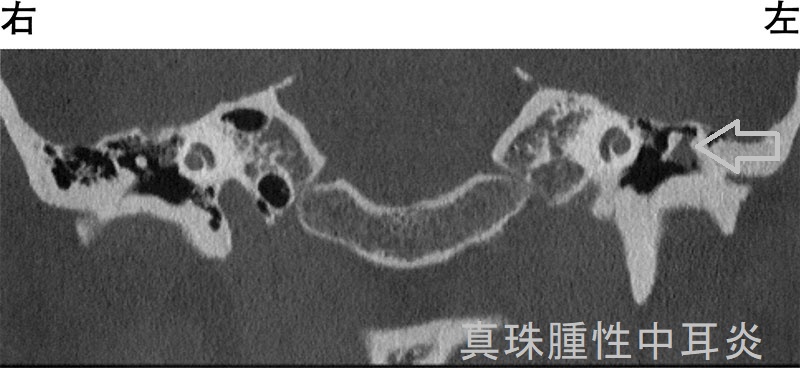

真珠腫性中耳炎(cholesteatomatous otitis media)は慢性中耳炎の重症型です。真珠腫とは、中耳側に凹んだ鼓膜の一部へ上皮細胞が侵入・増殖したもので、骨を溶かして進行します。

真珠腫の進行によって

- 伝導性難聴;耳小骨の破壊

- 感音性難聴・めまい;内耳の破壊

- 顔面神経麻痺

- 髄膜炎・脳膿瘍;頭蓋内へ浸潤

化膿性中耳炎と真珠腫性中耳炎に対する根治的治療は、真珠腫の摘出と鼓室形成術。